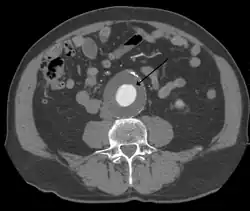

Abdominal aortic aneurysms (3,4 cm)

Abdominal aortic aneurysms (AAAs) are more common than their thoracic counterpart. One reason for this is that elastin, the principal load-bearing protein present in the wall of the aorta, is reduced in the abdominal aorta as compared to the thoracic aorta. Another is that the abdominal aorta does not possess vasa vasorum, the nutrient-supplying blood vessels within the wall of the aorta. Most AAA are true aneurysms that involve all three layers (tunica intima, tunica media and tunica adventitia). The prevalence of AAAs increases with age, with an average age of 65–70 at the time of diagnosis. AAAs have been attributed to atherosclerosis, though other factors are involved in their formation.[8] Risk factors for AAA include the male gender, aging, a history of smoking, hypercholesterolemia, and hypertension.[4][8][11] Reviews reported estimates for prevalence rates of AAA were 0.9-9% in men and 1–2% in women, where, generally, the incidence of AAA is four times greater in men compared to women at the same age.[4][8]

CT reconstruction image of an abdominal aortic aneurysm

The risk of rupture of an AAA is related to its diameter; once the aneurysm reaches about 5 cm, the yearly risk of rupture may exceed the risks of surgical repair for an average-risk patient. Rupture risk is also related to shape; so-called "fusiform" (long) aneurysms are considered less rupture-prone than "saccular" (shorter, bulbous) aneurysms, the latter having more wall tension in a particular location in the aneurysm wall.[12]